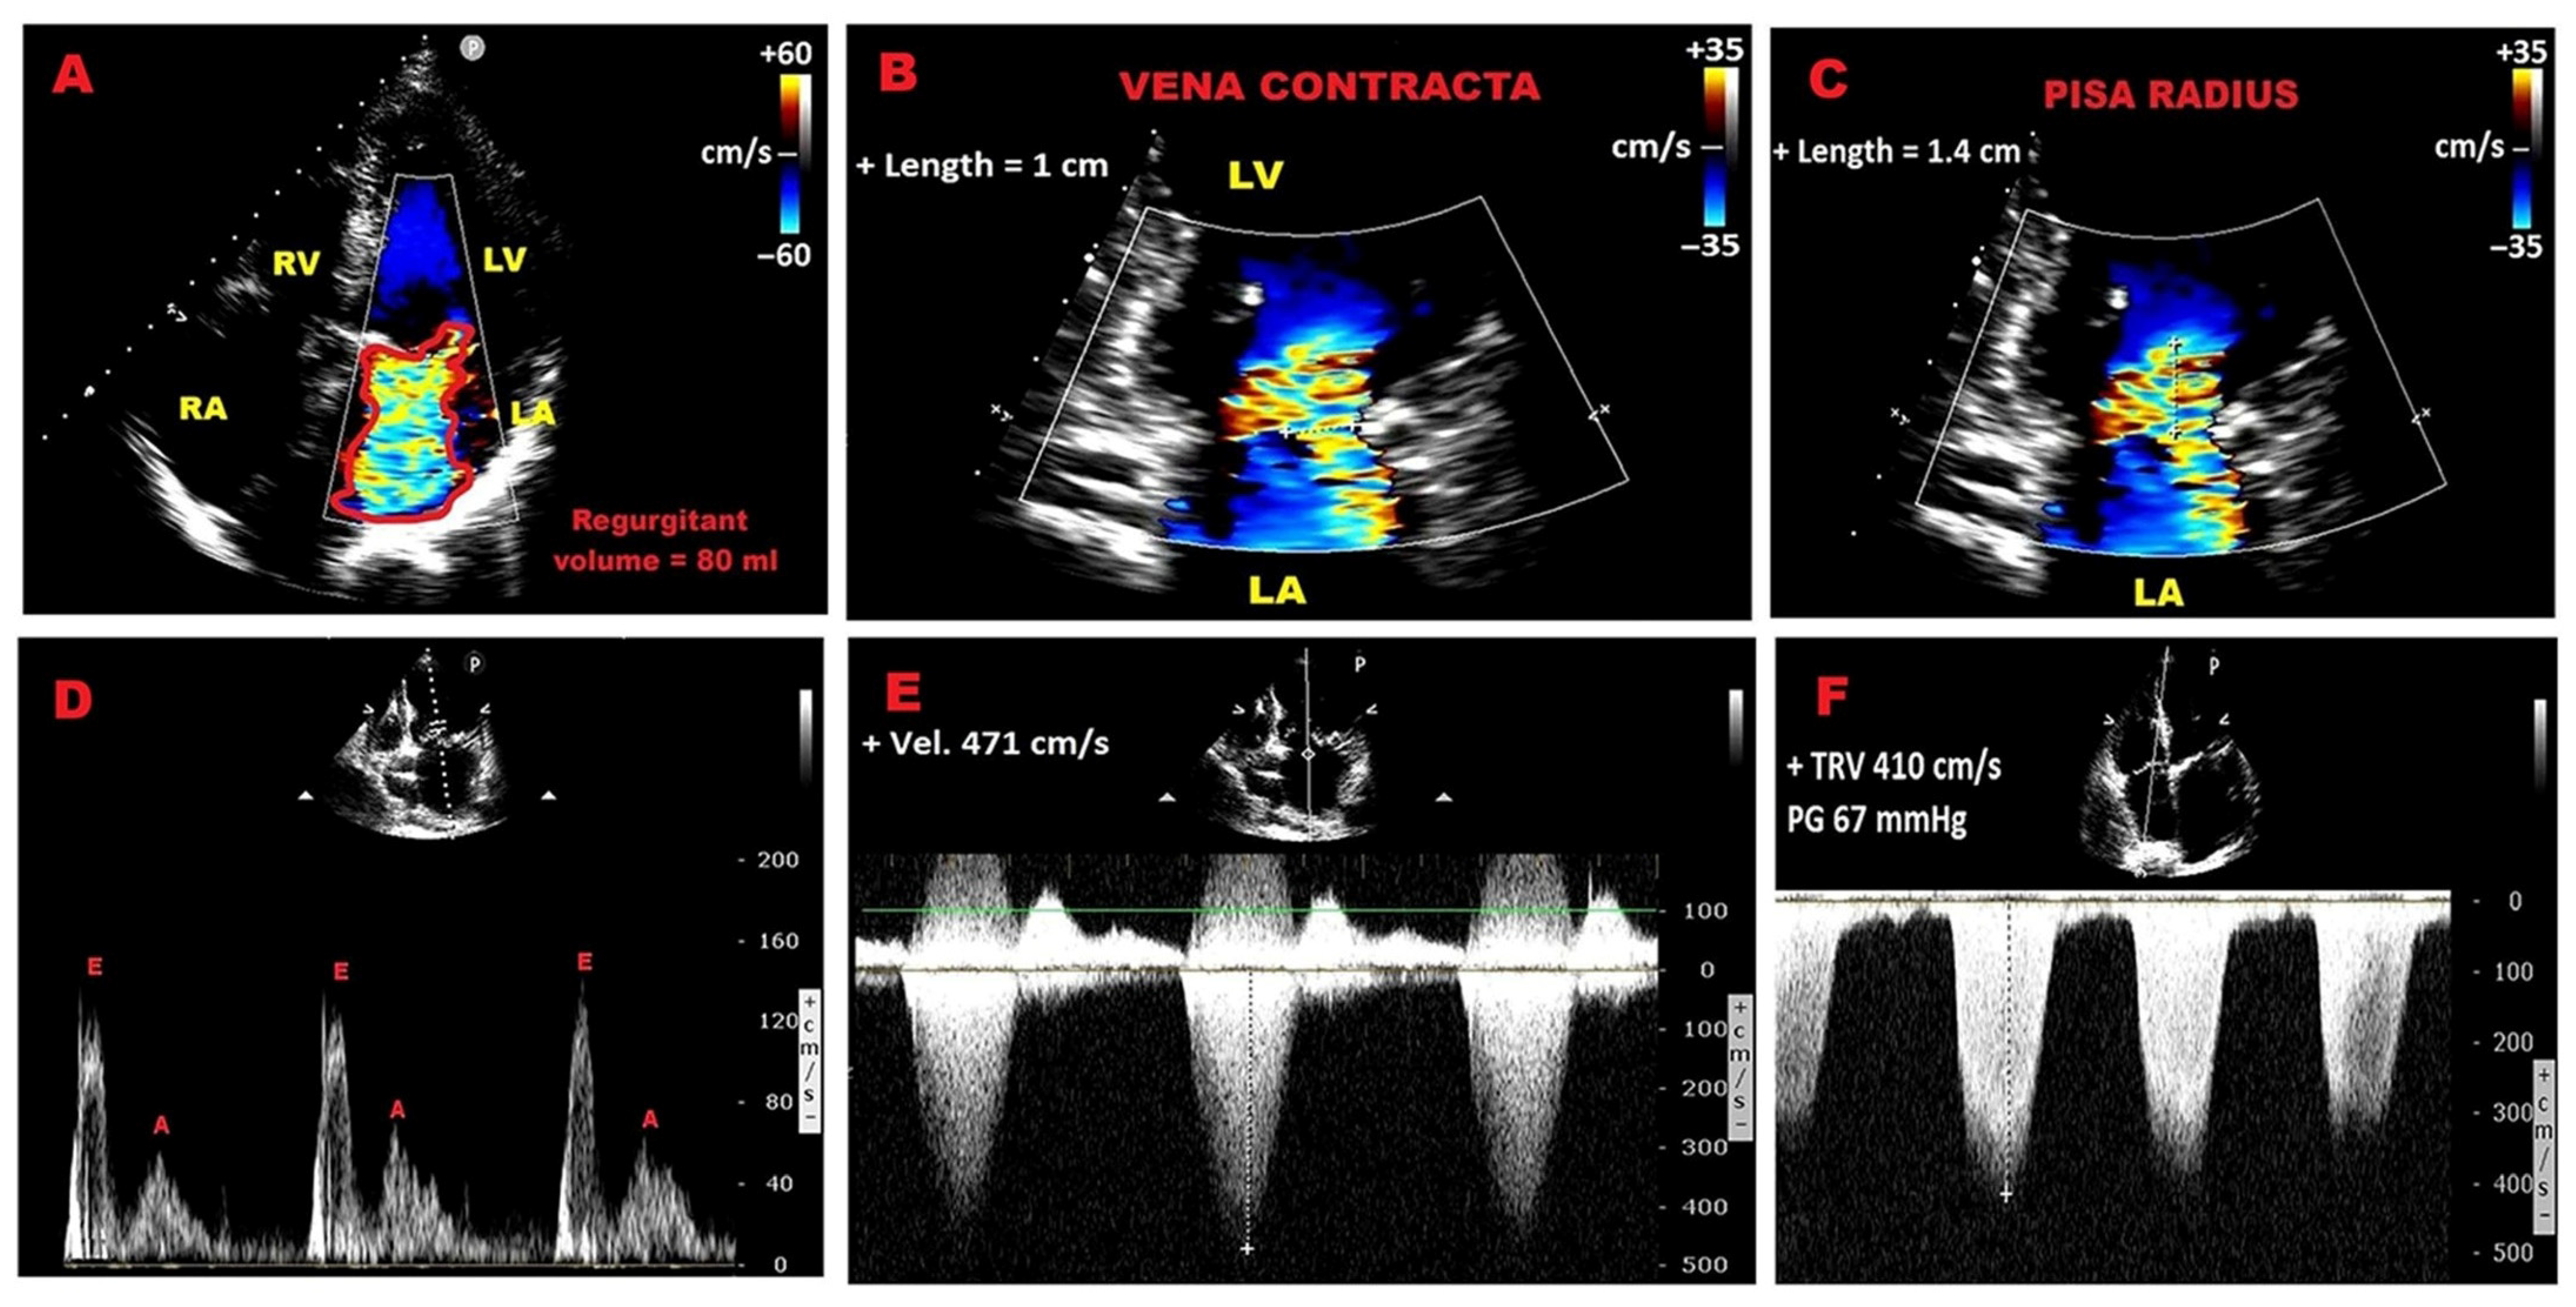

3.1. Echocardiographic Criteria of PMR Severity Recommended by Current Guidelines

3.7. Pulmonary Hypertension